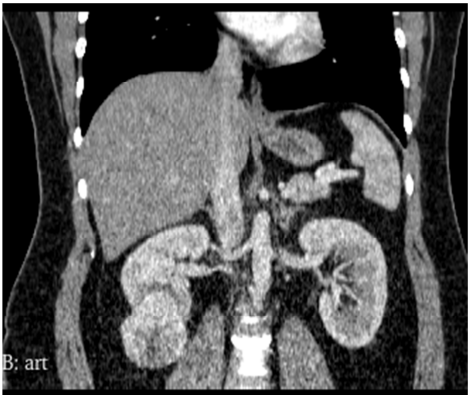

Homem de 56 anos de idade, hipertenso, diabético realizou tomografia de abdome, que demonstrou uma massa renal sólida, incidental, hipervascular, com 5,3 cm de diâmetro, no polo inferior do rim direito, distando 0,5 cm da via excretora. Qual a conduta mais adequada?